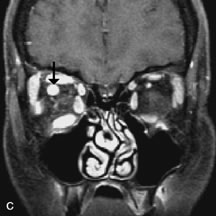

PATIENT PREPARATION Before MRI is performed, patients must be screened and prepared to avoid the potential hazards associated with the strong magnetic field. Patients who have ferrous aneurysm clips or cardiac pacemakers, who depend on life-support equipment, or who retain a possible metallic intraocular foreign body are not candidates for this imaging modality. MRI cannot be performed on obese patients who cannot fit into the bore of the magnet. Patients who are claustrophobic may not tolerate a prolonged period of study within the confines of the magnet, whereas others might do well if given a mild sedative. All worn metallic objects (e.g., necklaces, watches) should be taken off, credit cards set aside, and eye makeup removed before entering the room containing the magnet.5,20,34,35,36 NORMAL ORBITAL ANATOMY T1-weighted images provide the best anatomic details of the orbit because they display superior contrast resolution between normal structures (see Fig. 8). The vitreous has a long T1, resulting in an intermediate signal similar to brain, whereas the crystalline lens and sclera appear dark because of a longer T1 and short T2. The extraocular muscles, like all skeletal muscles, demonstrate a moderately long T1 and short T2 and highly contrast with the intense signal of the surrounding orbital fat (adipose tissue has an extremely short T1). The lacrimal glands appear as mottled areas of reduced intensity of the signal from the orbital fat in the lacrimal fossa. The optic nerves are seen with the same signal intensity as brain white matter and are hypointense relative to the orbital fat because their Tl is longer than the Tl of fat but shorter than the Tl of water. Cortical bone is not well delineated because it contains little free water, yielding minimal signal in MRI, and thus appears dark on all pulse sequences. This feature explains why MR images of the orbital apex and intracanalicular portion of the optic nerves are superior to comparable CT scans. Partial volume averaging of the bones in these regions obscures soft tissue details on CT images, whereas MRI reveals the signals only from the soft tissue structures with no cortical bone input. Bone marrow, on the other hand, is seen as a relatively intense signal because of its high fat content (see Fig. 8).37,38 T2-weighted pulse sequences are not ideal for imaging normal anatomy; however, they are particularly useful in revealing pathologic conditions (see Fig. 9). T2-weighted studies are most easily recognized by a bright vitreous signal. ORBITAL DISEASES Vascular Lesions Cavernous hemangiomas appear as well-circumscribed, smooth, usually intraconal masses that are isointense to muscle on T1-weighted images and hyperintense on T2-weighted images (Fig. 12). Patchy early enhancement is typically followed by diffuse, more homogeneous enhancement.39 The internal architecture of the mass, including septation and internal vasculature, may often be appreciated with high-quality orbital imaging.40 Lymphangiomas consist of ectatic vascular channels within a connective tissue stoma with varying degrees of lymphoid cellularity. On MRI, these tumors are typically poorly circumscribed, multicompartmental, and heterogeneous, often showing cystic dilations with fluid levels (Fig. 13). The signal characteristics within lymphangiomas vary considerably, reflecting cystic and solid components and the varying paramagnetic characteristics of blood at different stages of degradation.40–42 Acute hemorrhage appears hypointense on both T1- and T2-weighted formats. Methemoglobin present in subacute hemorrhage (3 to 14 days) leads to hyperintense signal on both T1- and T2-weighted images.41 A small percentage of lymphangiomas appear radiologically indistinct from orbital cavernous hemangiomas.43 Orbital varices are venous malformations that expand with increased systemic venous pressure, such as with Valsalva maneuvers. Because rapid acquisition of images during a Valsalva maneuver is important in imaging such a lesion, conventional or spiral CT is currently the modality of choice.44 MRI is an excellent modality for demonstrating enlargement of the cavernous sinus and dilation of the superior ophthalmic vein in patients with high-flow carotid-cavernous fistulas (Fig. 14).37MRA may be helpful in the evaluation of the venous outflow pattern. The rapidly flowing blood in these vascular structures carries the excited protons out of the section before they can be imaged, resulting in their dark appearance.5 In low-flow dural arteriovenous malformations, MRA may help define the arterial feeding vessels.45 Neural Lesions MRI is more effective than CT in delineating the intracranial optic nerves, chiasm, and optic tracts and, for this reason, is the preferred imaging modality in the evaluation of optic nerve disorders. The spatial relationships and image contrast of the orbital tissues with intraorbital optic nerve tumors is comparable between the two imaging modalities. The normal nerve is isointense to brain and appears enlarged and kinked owing to infiltration of an optic nerve glioma on T1-weighted images. Gliomas appear hyperintense on T2-weighted images and may be heterogeneous owing to cystic areas within the tumor. Contrast enhancement is variable.46 Intraorbital and intracranial optic nerve sheath meningiomas are usually isointense to cortical gray matter on Tl-weighted images and remain isointense on proton density studies (Fig. 15). Gd-DTPA is useful in delineating the intracranial extension of optic nerve meningiomas.7,47 The hyperostosis of bone and calcification associated with meningiomas are not demonstrated as well on MRI studies as on CT scans.20,37 Gd-DTPA–enhanced MRI also appears promising in the study of the permeability of the blood–brain barrier in selected optic neuropathies.22,48 MRI may reveal an enlarged optic nerve and some degree of contrast enhancement in cases of optic neuritis.49 Muscle Disorders Extraocular muscle enlargement in patients with thyroid-associated orbitopathy is demonstrated equally well with CT and MRI studies. However, the superior tissue contrast on MR images reveals better details of the relationships of the optic nerve to the thickened muscles at the orbital apex (Fig. 16).50 In addition, MRI may be able to differentiate between muscles that are enlarged as a result of edema and active inflammation and those enlarged because of fibrosis by their T2 relaxation times.21 Quantitative MRI was not found to be accurate in predicting the success of low-dose orbital irradiation.51 However, a muscular index relating the diameters of the rectus muscles to the bony orbital dimensions was useful in predicting optic nerve compression.52 MRI is also effective in imaging orbital tumors of mesenchymal origin, such as rhabdomyosarcoma, particularly in the assessment of extension into the anterior and middle cranial fossae (Fig. 17).37 The lack of any pathognomonic radiologic features necessitates rapid orbital biopsy when rhabdomyosarcoma is suspected. Osseous Lesions In general, CT is the imaging modality of choice when details of quantity and quality of bone are needed; however, abnormalities of bones can be detected indirectly by MRI. Cortical bone appears black (signal void) on MR images because of its low proton density and free-water content. The absence or discontinuity of the signal void of the orbital walls may represent bony destruction or fracture. Hyperostosis associated with prostate metastases or meningioma is visualized as areas of black smudging.50,53 Diseases in which the bone is replaced by pathologic tissues with a high free-water content, such as fibrous dysplasia, are well demonstrated on MRI. An intermediate signal intensity on T1-weighted images and hypointense signal on T2-weighted images is representative of fibrous dysplasia. Enhancement on post–Gd-DTPA MR scans is seen and is more evident in areas that are less mineralized.54 Cystic Lesions Dermoid cysts appear as rounded, well-defined lesions typically contiguous with an orbital bony suture. The high-intensity signal on T1-weighted images is attributed to the sebaceous-produced lipid contents (Fig. 18).31,50 Mucoceles may demonstrate a hypointense or hyperintense signal on MR images, depending on the concentration of proteinaceous or inflammatory fluid components. The integrity of the bony walls of the expanded sinus cavities cannot be assessed on MR as well as by CT.37,50,55,56 A high-signal intensity on Tl- and T2-weighted images is characteristic of orbital chronic hematic cysts because of the blood-breakdown products within the cysts.57 Trauma Although soft tissue relationships are usually better demonstrated on MRI, the evaluation of craniofacial bony trauma is preferable with CT. For example, prolapse of orbital fat through a fracture site and hemorrhage of adjacent tissues are demonstrated in an MR image, but the actual fractured bone is not imaged. Three-dimensional MRI of the orbit in subacute trauma has been described,58 although its precise role is not currently established. MRI has been suggested to be superior to CT in detecting intraorbital wooden foreign bodies.59,60 In a series of penetrating orbital injuries with organic foreign bodies, however, MRI was able to identify the foreign body in only four of seven cases.61 With an in vitro model for wood foreign body, McGuckin and colleagues concluded that CT was the imaging modality of choice.62 A careful history and, in selected cases, plain films to rule out a metallic foreign body are crucial before MRI is considered in patients with periocular trauma. MRI is particularly helpful in the detection and characterization of subperiosteal hematomas of the orbit (Fig. 19). They are most commonly seen in the subperiosteal space of the superior orbit as well-defined masses following a traumatic injury. The signal intensity varies depending on the acute, subacute, or chronic nature of the hematoma, based on the stage of blood degradation. Fresh hemorrhages are hypointense on T1-weighted images and hyperintense on T2 images. Hematomas that are 1 to 7 days old are hypointense on both T1- and T2-weighted images. T1-weighted images of hematomas more than a week old are hyperintense due to the oxidation of deoxyhemoglobin to methemoglobin, whereas the T2 images remain hypointense.63 Metastatic Tumors Breast carcinoma metastatic to the orbit has been demonstrated to be hypointense to the surrounding orbital fat on T1-weighted studies and hyperintense on T2-weighted images and has an affinity to the extraocular muscles (Fig. 20).50,64 The MRI characteristics of prostate carcinoma metastatic to the orbit have been described as involving the greater and lesser wing of the sphenoid, orbital roof, and optic canal. Diffuse bone hypertrophy with isointense or slightly hyperintense tissue on T1-weighted images represents the osteoblastic carcinomatous bone infiltration. Contrast enhancement is variable on T1-weighted and fat-suppressed images.65 Most other metastatic tumors also have a lower intensity signal on T1-weighted images and appear to displace or infiltrate normal orbital structures; however, their signal characteristics are variable on T2-weighted MR images.66 Many metastatic tumors demonstrate bright contrast enhancement with Gd-DTPA. Infectious Disorders MRI findings of preseptal and orbital cellulitis typically include increased signal intensities on T2-weighted images of the eyelids and orbital fat, respectively, due to the increased water content of the tissues. Since most cases of bacterial orbital cellulitis are associated with paranasal sinusitis, hyperintense signals of the affected sinuses may also be found on T2-weighted images as well as enhancement of polyps and granulation tissue on postgadolinium T1-weighted MR images. Subperiosteal abscess formation may occur due to contiguous spread of infection from the paranasal sinuses and appear on MRI as an area of intermediate signal on T1-weighted and proton-weighted MR images. The abscess may appear slightly hyperintense compared with muscle on T2-weighted scans with the necrotic contents having the greatest intensity.67 MRI and MRV are more sensitive than CT in revealing cavernous sinus thrombosis. Engorgement of the cavernous sinus, extraocular muscles, and ophthalmic veins is seen with hyperintensity of the thrombosed sinuses evident on all pulse sequences. The enlarged, thrombosed superior ophthalmic vein appears less hypointense than the normal contralateral ophthalmic vein, and hyperintensity within the lumen of the vessel may be seen on T1- and T2-weighted MR images.68 Inflammatory and Lymphoproliferative Lesions Inflammatory conditions of the orbit, both idiopathic (inflammatory pseudotumor) and those of known causes, have been found to be hypointense to fat and isointense to muscle on Tl-weighted studies and isointense or slightly hyperintense to fat on T2-weighted images (Fig. 21).50,64,69 The more fibrous or sclerosing varieties have less signal intensity on T2-weighted images. Marked enhancement is seen in pseudotumor infiltrates after gadolinium administration.70 The same signal characteristics are demonstrated in patients with Tolosa-Hunt syndrome, with mass lesions seen in the cavernous sinuses and orbital apices.71 Lymphomas have MRI characteristics similar to those of inflammatory lesions in that they are hypointense to fat and isointense to muscle on T1-weighted images (Fig. 22). They may appear hyperintense to fat on T2-weighted images, perhaps owing to less fibrosis than that seen in orbital inflammatory pseudotumor, although this is not a consistent finding.31,50,66 Lymphoid tumors typically enhance moderately after contrast injection. Unfortunately, studies have shown that tumor density and homogeneity are similar between inflammatory and malignant orbital infiltrates, and MRI cannot differentiate these lesions.72,73 Lacrimal Gland Tumors Lacrimal gland lesions present special problems in diagnosis and management. Pleomorphic adenoma (benign mixed tumor) should not be biopsied, but rather excised in toto. On the other hand, for lymphoma and inflammatory infiltrates, incisional biopsy is more appropriate than complete excision of the lacrimal gland. Thus, preoperative clinical and radiologic evaluation are especially crucial in planning appropriate surgical management. Pleomorphic adenomas demonstrate long T1 and T2 signal characteristics. They may show heterogeneity on T2-weighted images74 and moderate to marked enhancement with contrast.75 Signal characteristics of adenoid cystic carcinoma include hypointensity to fat on T1-weighted images, hyperintensity to fat with increased T2 weighting, and isointensity to fat on proton density-weighted studies (Fig. 23).31,75 Secondary bony alterations of the lacrimal fossa associated with lacrimal gland tumors, such as remodeling (benign mixed tumor) or destruction (adenoid cystic carcinoma), are seen indirectly on MR images; however, bone windows on CT scans provide better delineation of these changes. In contrast to the round or globular appearance of benign or malignant epithelial tumors of the lacrimal gland, lymphoproliferative tumors usually appear to be molding or draping onto the globe and the surrounding bony orbit. LACRIMAL DRAINAGE SYSTEM DISORDERS MRI with surface coils provides excellent spatial resolution and tissue-specific signal intensities of the lacrimal drainage system. These parameters have been found useful to more accurately demonstrate the extent of lesions in the lacrimal sac and differentiate long-standing mucoceles from solid tumors than CT.76 Physiologic studies in patients with tearing disorders now include MR dacryocystography, in which Gd-DTPA is either placed topically in the conjunctival fornix or injected by cannulation into the lacrimal sac. They provide a detailed morphologic and functional analysis of the lacrimal excretory system; however, they are no more sensitive than digital-subtraction dacryocystography or CT dacryocystography.77–79 INTRAOCULAR TUMORS On MRI, uveal melanomas have a typical appearance that helps to differentiate them from other primary and secondary intraocular tumors as well as choroidal detachments. Pigmented melanomas are hyperintense on Tl-weighted images, hypointense on T2-weighted studies, and hyperintense on proton density–weighted examinations (Fig. 24).30,31,50,80–82 These signal characteristics have been attributed to the paramagnetic properties of melanin because of stable free radicals that shorten the T1 and T2 relaxation times. Moderate enhancement is seen on postgadolinium T2-weighted images. Gadolinium-enhanced T1-weighted images are particularly sensitive in detecting choroidal melanomas.83 MRI may be less sensitive in detecting extrascleral extension of tumor than echography performed by an experienced ultrasonographer.84 Tumors metastatic to the choroid are hyperintense on T1- and T2-weighted images.24 The signal characteristics, however, may be similar to those seen with choroidal melanoma. Choroidal hemangiomas, on the other hand, have an intermediate signal on T1-weighted sequences and become hyperintense on T2-weighted images50 as well as proton density–weighted images.81 Retinoblastomas display moderate signal intensity on T1-weighted studies and a low signal on T2-weighted images.31,80,85 Calcification can be easily detected by CT and ocular ultrasonography but is not imaged by MRI.25,50 The presence of optic nerve involvement is best evaluated by MRI. ACQUIRED ANOPHTHALMIA When an eye is removed owing to tumor or trauma, an implant is typically placed in the intraconal space. MRI may be useful in defining the size, shape, and position of such orbital implants.86 Porous hydroxyapatite or polyethylene implants are preferred by many surgeons performing enucleation or evisceration. A porous implant offers the possibility of supporting a motility coupling peg to increase the movement of the overlying prosthesis. MRI with contrast is used by some surgeons to evaluate the degree of fibrovascular ingrowth in hydroxyapatite87 and porous polyethylene88 implants prior to motility peg placement. |